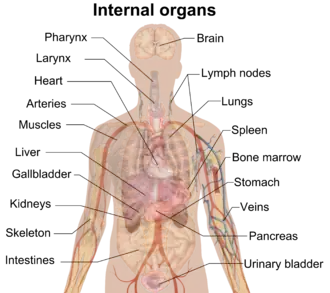

Many of the internal organs of the human body | |

In a multicellular organism, an organ is a collection of tissues joined in a structural unit to serve a common function.[1] In the hierarchy of life, an organ lies between tissue and an organ system. Tissues are formed from same type cells to act together in a function. Tissues of different types combine to form an organ which has a specific function. The intestinal wall for example is formed by epithelial tissue and smooth muscle tissue.[2] Two or more organs working together in the execution of a specific body function form an organ system, also called a biological system or body system.

The number of organs in any organism depends on the definition used. There are approximately 79 organs in the human body; the precise count is debated.[4]

Animals

Except for placozoans, multicellular animals including humans have a variety of organ systems. These specific systems are widely studied in human anatomy. The functions of these organ systems often share significant overlap. For instance, the nervous and endocrine system both operate via a shared organ, the hypothalamus. For this reason, the two systems are combined and studied as the neuroendocrine system. The same is true for the musculoskeletal system because of the relationship between the muscular and skeletal systems.

- Cardiovascular system: pumping and channeling blood to and from the body and lungs with heart, blood and blood vessels.

- Digestive system: digestion and processing food with salivary glands, esophagus, stomach, liver, gallbladder, pancreas, intestines, colon, mesentery, rectum and anus.

- Endocrine system: communication within the body using hormones made by endocrine glands such as the hypothalamus, pituitary gland, pineal body or pineal gland, thyroid, parathyroids and adrenals, i.e., adrenal glands.

- Excretory system: kidneys, ureters, bladder and urethra involved in fluid balance, electrolyte balance and excretion of urine.

- Lymphatic system: structures involved in the transfer of lymph between tissues and the blood stream, the lymph and the nodes and vessels that transport it including the immune system: defending against disease-causing agents with leukocytes, tonsils, adenoids, thymus and spleen.

- Integumentary system: skin, hair and nails of mammals. Also scales of fish, reptiles, and birds, and feathers of birds.

- Muscular system: movement with muscles.

- Nervous system: collecting, transferring and processing information with brain, spinal cord and nerves.

- Reproductive system: the sex organs, such as ovaries, oviducts, uterus, vulva, vagina, testicles, vasa deferentia, seminal vesicles, prostate and penis.

- Respiratory system: the organs used for breathing, the pharynx, larynx, trachea, bronchi, lungs and diaphragm.

- Skeletal system: structural support and protection with bones, cartilage, ligaments and tendons.